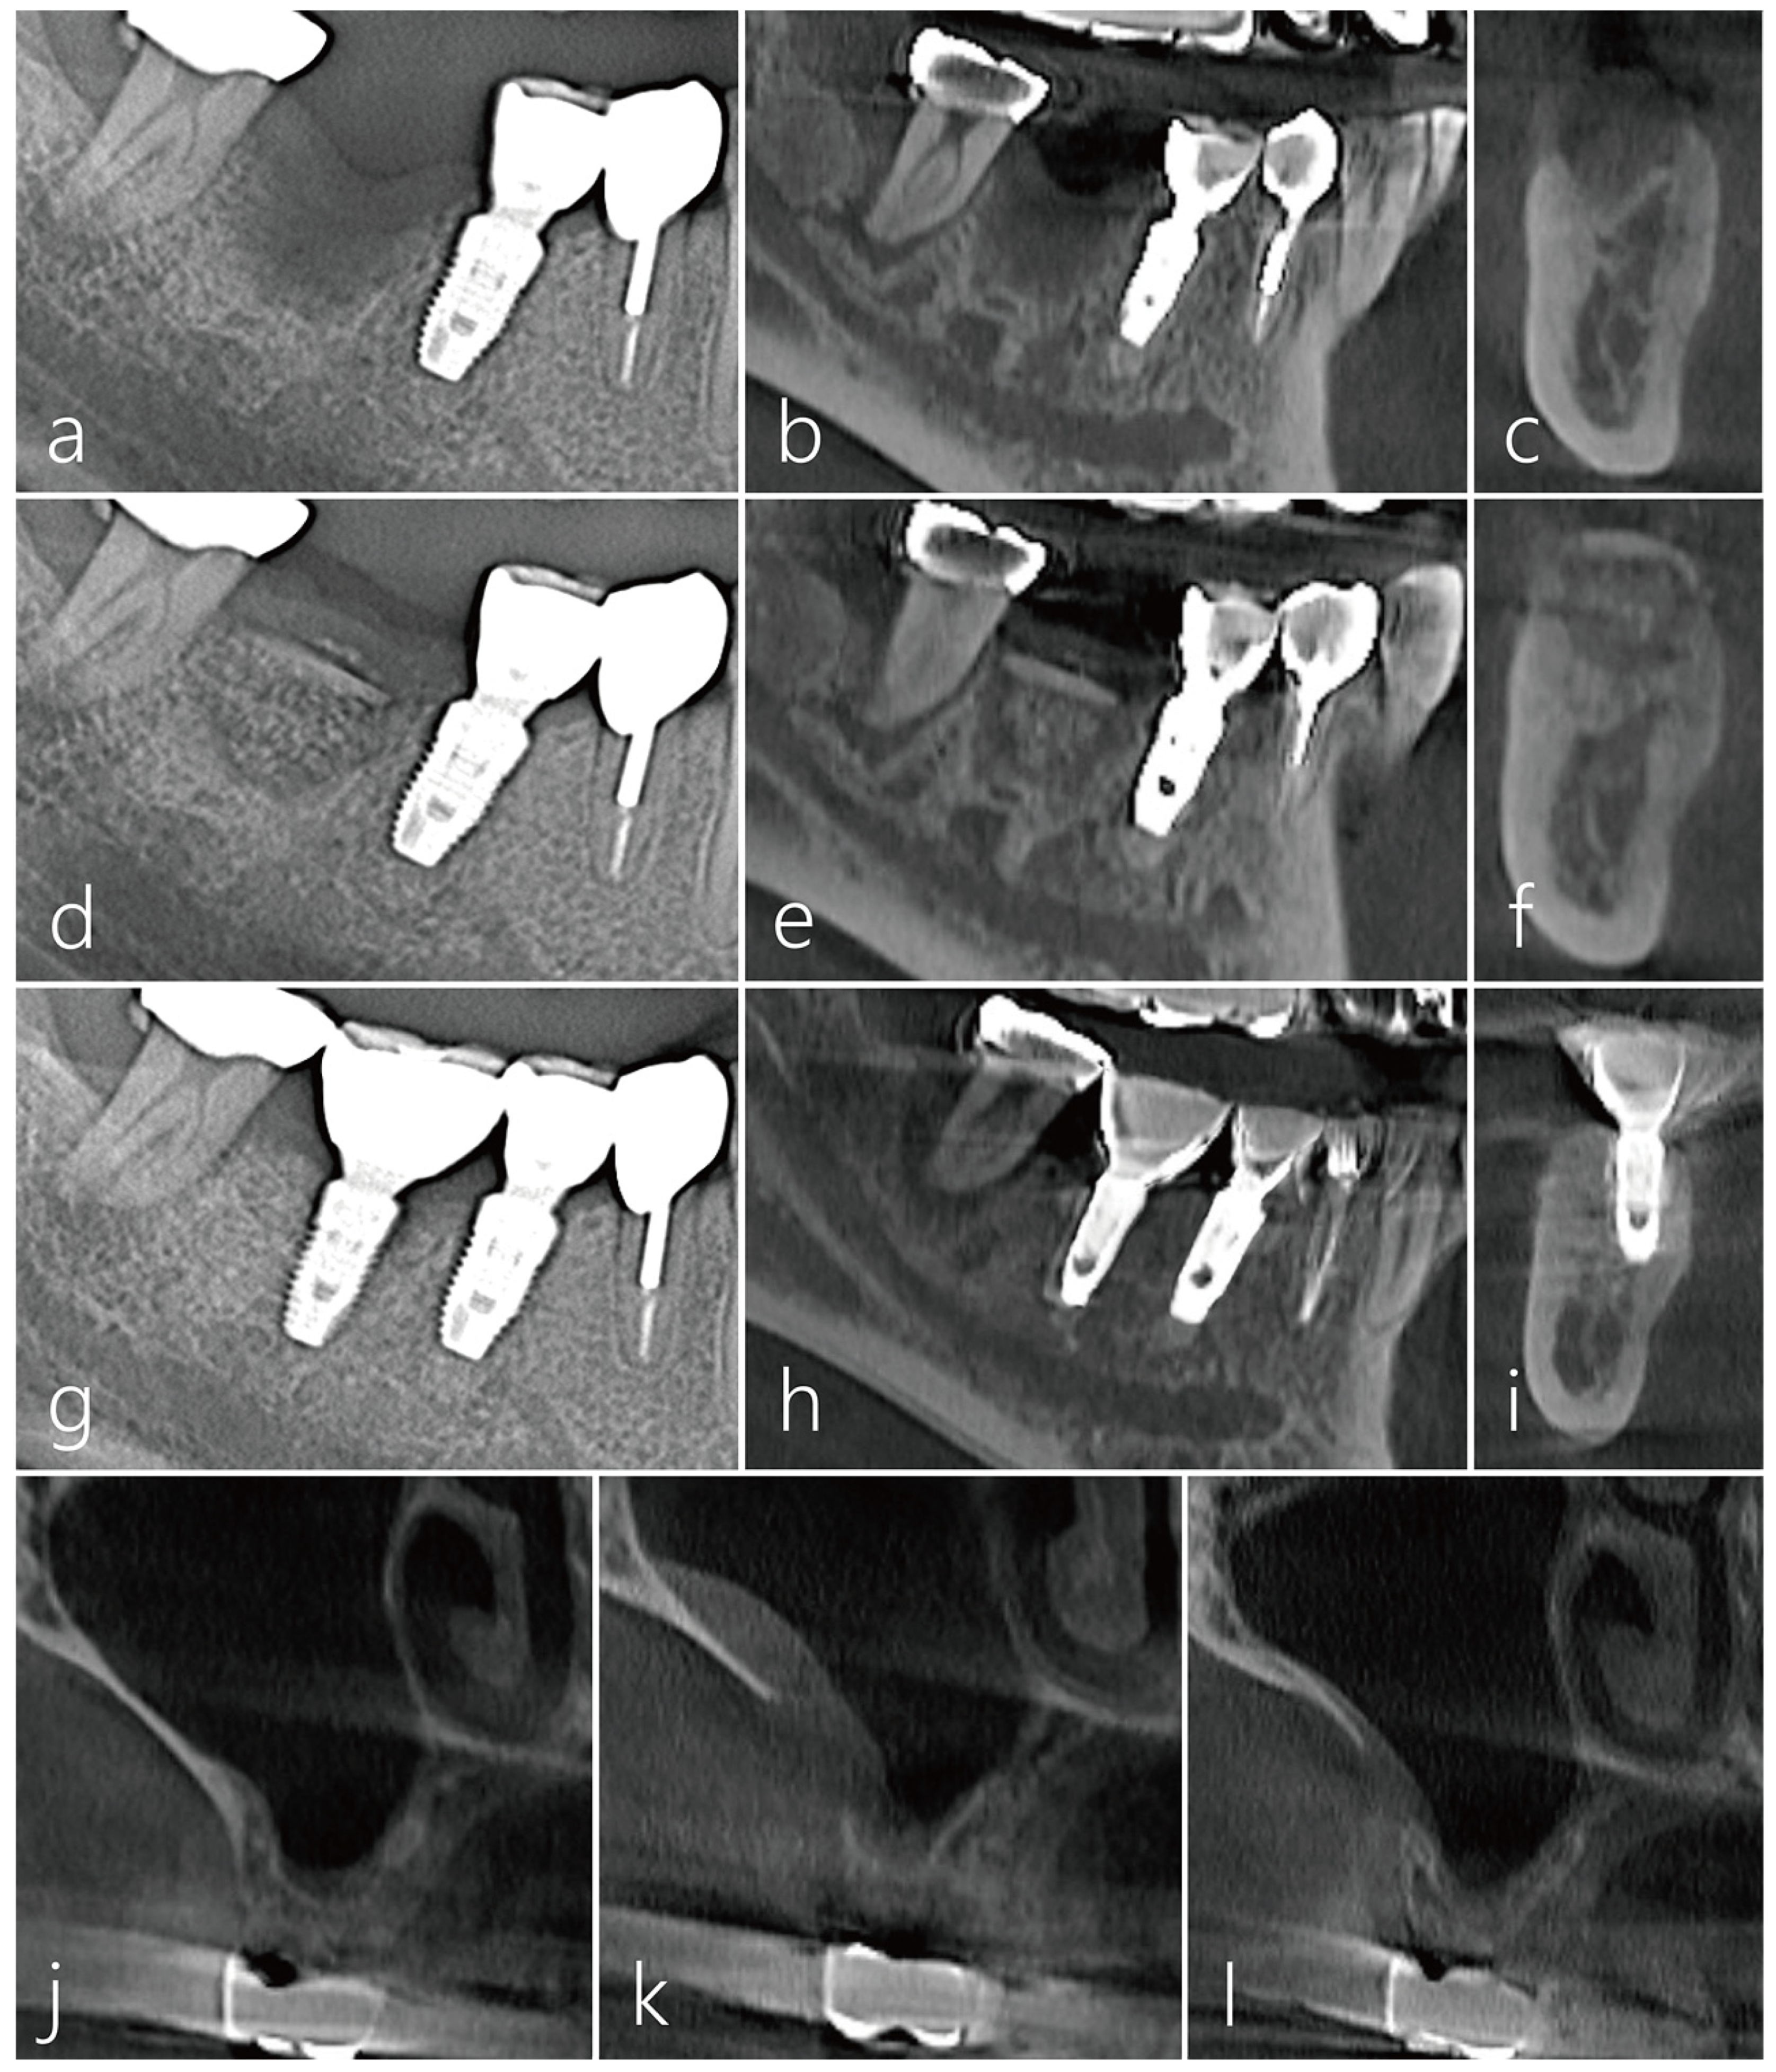

2.2. Case 2

This patient, a 48-year-old male smoker, developed severe bone resorption and tooth mobility due to advanced periodontitis in the right mandibular second molar (Figure 7a). After 2 months of tooth extraction, VRA with the bone bridge technique was performed. A simultaneous implant placement was also planned for the #26 tooth missing area. On the panoramic radiograph taken 2 months after tooth extraction, severe vertical ridge deficiency was evident (Figure 7b). A decision was made to use the lateral sinus bony window on the contralateral side as a source of bone block graft, as the implant placement at the #26 site was also planned.

Figure 7.

Case 2. (a) Severe bone resorption and tooth mobility occurred due to advanced periodontitis in #47 tooth; (b) On the panoramic radiography taken 2 months after tooth extraction, vertical ridge deficiency was very severe. A decision was made to use the lateral sinus bony window on the contralateral side as a bone block graft donor; (c) A bone bridge was achieved by immobilizing the harvested lateral sinus bony window to the proximal bone of the adjacent teeth by the press-fit method. The bone graft substitute was not filled in the gap space between the defect and the bone bridge; (d) On the panoramic radiography taken 6 months after the bone bridge technique, the transplanted bone was well incorporated with the adjacent native bone, and there was no movement during implant site preparation; (e) Panoramic radiography taken after implant placement; (f) In periapical radiography taken 1 year after prosthesis delivery, crestal bone loss around the implant was not observed, and bone remodeling was well done in the space between the bone bridge and the post-extraction socket; (g) CBCT image of the donor site taken immediately after surgery; (h) CBCT image of the donor site after prosthesis placement; (i) The size of the donor site was greatly reduced in the CBCT coronal image taken 1 year after the implant prosthesis was delivered.

The immobilization of the bone bridge was achieved by fixing the harvested bone to the proximal bone of the adjacent teeth by the press-fit method. Unlike the previous case, the gap between the defect and the bone bridge was not filled with any bone graft substitute; the defect morphology was well circumscribed and contained. (Figure 7c). The panoramic radiograph taken 6 months after the bone bridge technique did not show any signs of surface resorption of the bone bridge (Figure 7d). The bone bridge was well incorporated with the adjacent native bone, and no mobility of the bone bridge was observed during the implant placement (Figure 7e). Uncovering was performed 4 months after implant placement, and prosthesis was delivered 2 months later. In the periapical radiograph taken 1 year after prosthesis delivery, crestal bone loss around the implant was not observed, and bone remodeling was well achieved in the space between the bone bridge and the post-extraction defect (Figure 7f). The healing of the donor site was observed on the coronal images of CBCT. In the coronal image of the CBCT taken after bone harvest, the lateral sinus window was very thick, and it was considered an ideal thickness (Figure 7g). No abnormal finding was observed in the maxillary sinus in the CBCT taken after the #26 implant prosthesis was delivered (Figure 7h). The donor site had fully healed with new bone as evident in the CBCT taken 1 year after the #26 implant prosthesis was delivered (Figure 7i).

2.3. Case 3

A 61-year-old male non-smoker without significant medical history had #16 extracted 3 months prior and presented a post-extraction socket with a severe vertical ridge deficiency (Figure 8a). The #17 tooth was also extracted, and the bone bridge technique was performed using the lateral bony window of the maxillary sinus along with particulate grafts to prevent any dead space formation (Figure 8b). After 6 months of healing, two Ø 4.3 × 10 mm SLA-textured implants (Implantium, Dentium, Suwon, Republic of Korea) were placed. The bone bridge was well integrated with the adjacent native bone. Uncovering was performed after 4 months, and the prosthesis was delivered after 2 months (Figure 8c). In the panoramic radiograph taken 7 years after prosthesis delivery, the crestal bone level was still well maintained, and the implants were stable (Figure 8d). No abnormal findings were found in follow-up CBCT images (Figure 8e,f). In the sagittal image of CBCT taken 7 years after the prosthesis was delivered, the crestal bone level around the implant was well maintained (Figure 8g). The donor site in the lateral wall of the maxillary sinus was healing with new bone formation to close the communication (Figure 8h–j).

Figure 8.

Case 3. (a) A localized post-extraction socket with severe vertical ridge deficiency was observed on a panoramic radiography taken 3 months after #16 tooth extraction; (b) The patient’s #17 tooth was also extracted, a bone bridge was prepared using the lateral sinus window of the maxillary sinus, and particulate bone was filled to reduce the dead space; (c) Two implants were placed 6 months after surgery. The bone bridge was well integrated with the adjacent native bone. Uncovering was performed after 4 months, and the prosthesis was delivered after 2 months; (d) Vertical bone augmentation of the compromised post-extraction socket was well achieved in the panoramic radiography taken 7 years after prosthesis delivery; (e) Sagittal image of CBCT taken immediately after the bone bridge technique; (f) Sagittal image of CBCT taken after prosthesis delivery; (g) In the CBCT sagittal image taken 7 years after prosthesis delivery, the crestal bone level around the implant was well maintained; (h) In the coronal image of CBCT taken after bone bridge technique, a donor site was observed; (i) The size of the donor site was reduced in the coronal image of CBCT taken after the prosthesis was delivered; (j) Only a small trace of the donor site was observed in the coronal image of CBCT taken 7 years after prosthesis delivery.